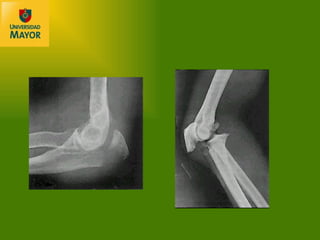

FRACTURAS DEL OLECRANON. Bastante común en codo  desconocen incidencia %?. Mecanismo: golpe directo o caída.

Clasificación: Intraarticulares.  Razgo transverso, sea simple o complejo. Razgo oblicuo Conminutas, que poseen lesiones asociadas como extensión a distal de la FX. o  lesión de la cúpula radial. Extraarticulares. Fx avulsivas de la punta del olecranon.

Clasificación: No desplazadas , manejo ortopédico con cabestrillo o yeso a 90° por 3 a 4 semanas. Desplazadas : deben diferenciarse en estables o no estables. Estables : con conminución menor al 60%, OTS de neutralización (Banda de tensión) y si hay mas del 60% de conminucion, se reseca y OTS con placa. Inestables :  no conminuta, OTS con placa Conminuta: neutralización y placa.

Tratamiento  La mayoría de las veces Obenque ( alambres con amarra en 8)